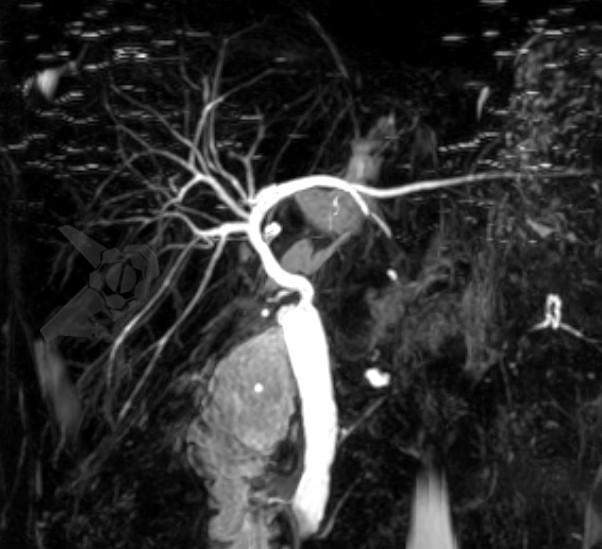

Foi submetida a ressonância magnética de abdome (RNM) com colangiorressonância (colangioRNM), que não evidenciou alteração vascular da artéria hepática, apenas desproporção entre as vias biliares do doador e receptor, sem estenose definida, porém com discreta dilatação de vias intra-hepáticas.